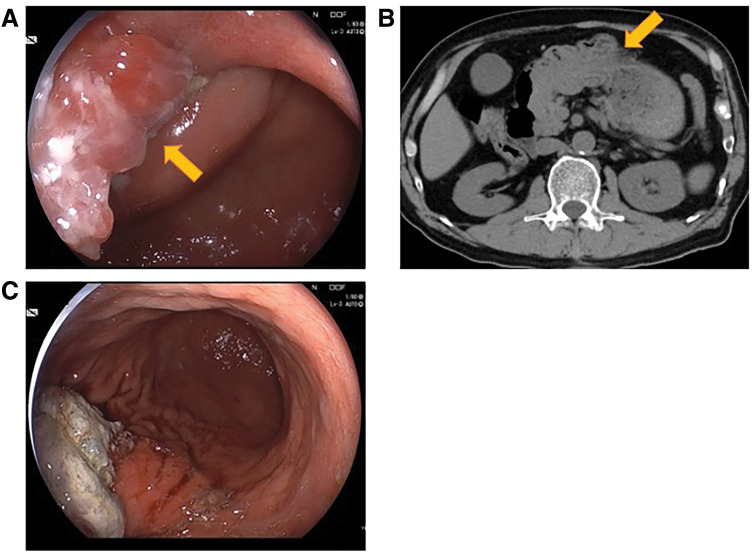

Case presentation: A 69-year-old man with a 30-mm tumor arising from the posterior wall of the gastric body was scheduled for elective surgery. During hospitalization for diabetes mellitus management, he developed sudden epigastric pain and nausea. Upper gastrointestinal endoscopy revealed tumor prolapse into the duodenum, leading to a diagnosis of ball valve syndrome. After successful endoscopic reduction, open local gastrectomy was performed. Pathological examination confirmed a well-differentiated tubular adenocarcinoma, classified as pT1b (SM2) N0M0, pStage IA.